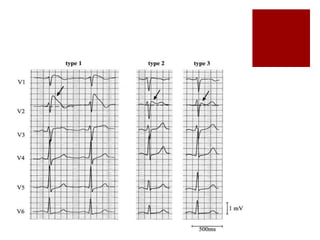

Brugada Syndrome

QRS Complex  Duration N= 70-100ms narrow (Supraventricular) wide (ventricular or SVT with aberrant conduction)  Amplitude High voltage eg LVH Low voltage Alternans eg pericardial effusion  Morphology Notched RBBB LBBB  Spot Diagnoses Brugada Syndrome WPW Syndrome (delta waves) Tricyclic poisoning (wide QRS + dom R in aVR